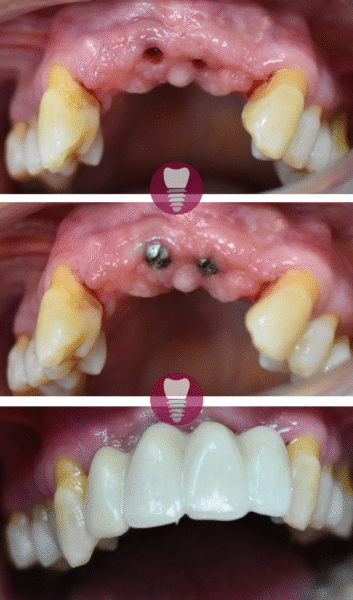

Este caso clínico muestra un tratamiento de restauración completa de la dentadura superior. Este tipo de intervención es ideal para pacientes que presentan una pérdida significativa de piezas dentales en la arcada superior o que tienen dientes gravemente dañados debido a caries avanzadas, desgaste, o problemas periodontales.

En este tratamiento, se emplea una prótesis sobre barra en implantes, proporcionando una solución estable y estética que permite recuperar la funcionalidad y la apariencia de la sonrisa. Este enfoque no solo mejora la capacidad de masticación del paciente, sino que también refuerza la estructura facial y restaura la confianza en su aspecto.

Gracias a la planificación digital y los materiales de alta calidad utilizados, el resultado es duradero y natural.